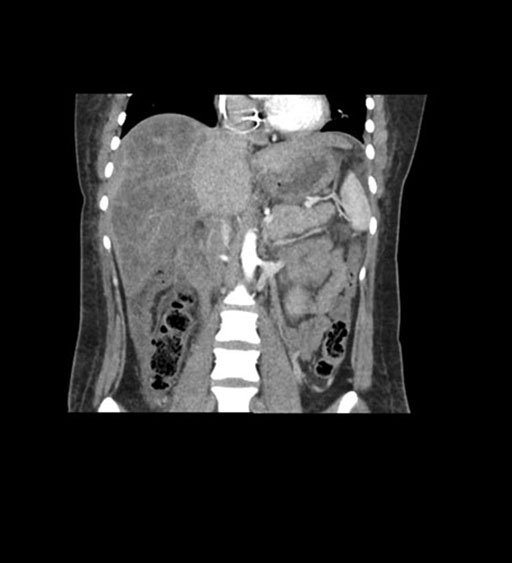

Imaging Analysis

Look through the patient's CT scan to identify any areas of concern for the necessary procedure.

Coronal Arterial

Coronal Venous